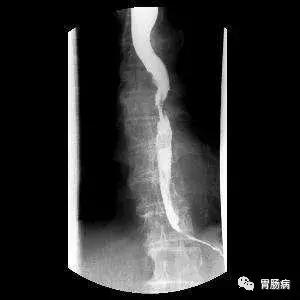

1、X线钡餐检查,也叫食管片。优点是简便,准确性高,病人痛苦少,不但可观察食管病灶部位,长度,梗阻程度,溃疡大小与深度,有无穿孔和瘘管形成,而且可观察食管粘膜和食管动力学改变。